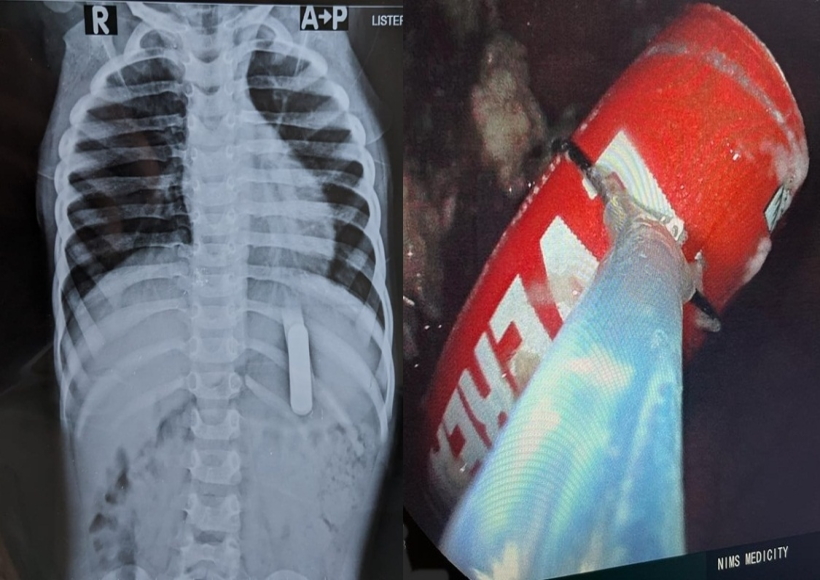

तिरुवनंतपुरम, 19 दिसंबर (युआईटीवी/आईएएनएस)| केरल की राजधानी के बाहरी इलाके में स्थित एक निजी अस्पताल के डॉक्टरों ने सावधानीपूर्वक 2 साल के बच्चे के पेट से टीवी रिमोट की बैटरी निकाली, जिसे वह गलती से निगल गया था। एनआईएमएस अस्पताल के गैस्ट्रोएंटेरोलॉजिस्ट जयकुमार ने आईएएनएस से बात करते हुए कहा कि हम वक्त रहते एंडोस्कोपी के माध्यम से पेट से बैटरी को निकालने में कामयाब हुए।

उन्होंने कहा, बच्चे ऋषिकेश को उसके माता-पिता पहले अपने घर के पास एक स्थानीय अस्पताल में ले गए थे, उसके बाद यहां ले आए। जब हमने सुना कि क्या हुआ है, हमने तुरंत ऑपरेशन थियेटर को अलर्ट किया और बच्चे को एनेस्थीसिया दिया। करीब 20 मिनट में उनके पेट से बैटरी निकाल ली गई। अगर समय की थोड़ी देरी होती, तो बड़ी मुश्किल हो जाती।

जयकुमार ने कहा, बच्चा अब तंदुरुस्त है।

टीवी के रिमोट में इस्तेमाल होने वाली पांच सेंटीमीटर लंबी और डेढ़ सेंटीमीटर चौड़ी बैटरी को बच्चे ने खेलते समय निगल लिया।